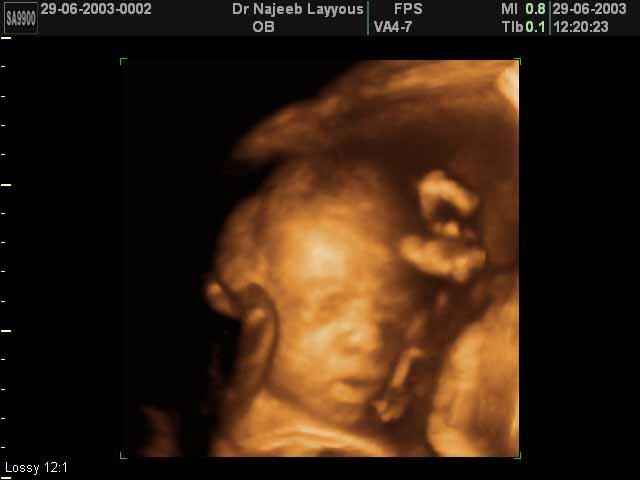

- صور لوجه الجنين في داخل الرحم

- صور جانبية لرأس الجنين

صور لوجه الجنين بجهاز الالتراساوند ثلاثي الأبعاد | الدكتور نجيب ليوس